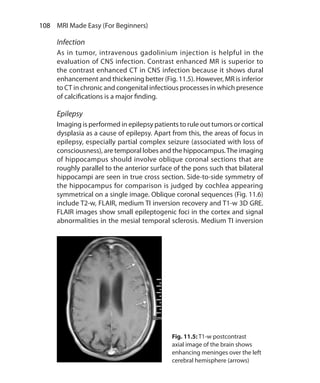

Chapter 11.  Principles of Interpretation: Neuroimaging	 102

Sequence Selection	 103